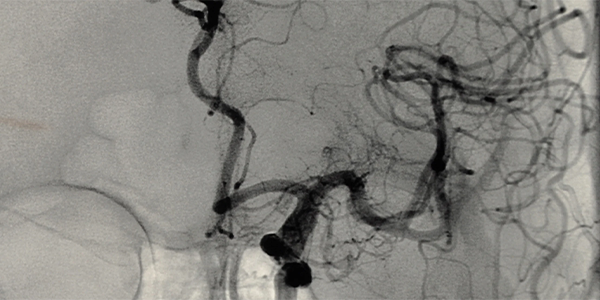

Serebral anjiyografi, beyindeki kan damarlarının görüntülerini elde etmek için kullanılan bir görüntüleme yöntemidir. Bu işlemde, kasıktaki femoral arter veya koldaki radyal arter gibi bir atardamardan ince bir kateter (plastik bir tüp) girilir ve bu kateter x-ışını görüntüleme kılavuzluğunda beyindeki kan damarlarına kadar ilerletilir. Kateter aracılığıyla kan damarlarına kontrast madde enjekte edilir ve x-ışını görüntüleri çekilir. Bu görüntüler, beyindeki kan damarlarının yapısını ve kan akışını detaylı bir şekilde gösterir.

Serebral anjiyografi işlemi, genellikle bir radyoloji laboratuvarında yapılır. İşlem sırasında hasta bir masaya yatırılır. Girişim yapılacak bölge (kasık veya kol) temizlenir ve lokal anestezi uygulanır. Anestezinin etki etmesinin ardından, ince bir iğne ile atardamara girilir ve bir kateter yerleştirilir. Kateter, x-ışını görüntüleme kılavuzluğunda beyindeki kan damarlarına kadar ilerletilir. Kateter aracılığıyla kan damarlarına kontrast madde enjekte edilir ve x-ışını görüntüleri çekilir. İşlem sonunda, kateter çıkarılır ve girişim yapılan bölgeye baskı uygulanarak kanama durdurulur. Hasta birkaç saat gözlem altında tutulur.